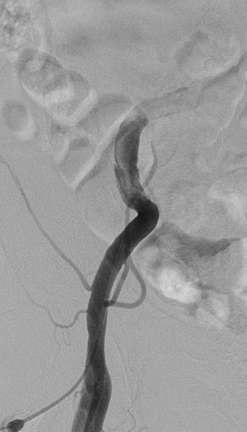

导管操作导致髂外动脉出血